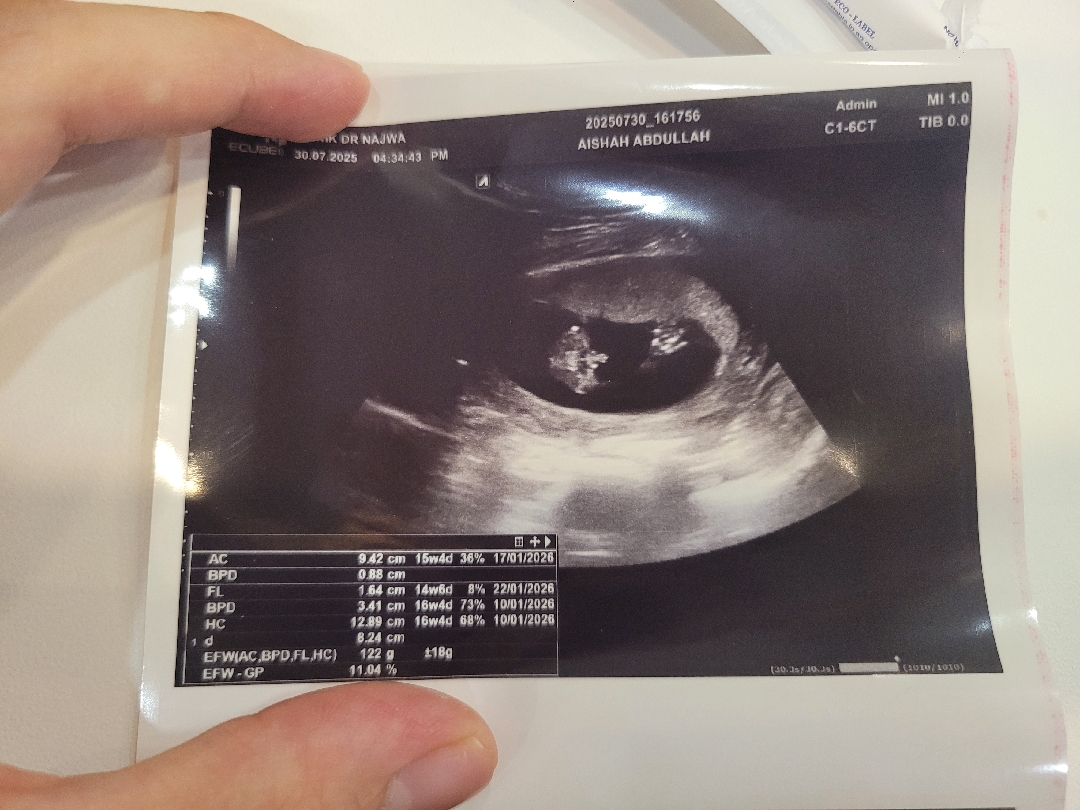

16주이지만 반전없는 아들맘 확정

16주라 혹시 반전없겠냐 하니까 너무나도 그(?)모양을 하고 있기에 의사선생님이 그럴일 없을 것 같다고ㅎㅎㅎㅎ 요즘 딸들 많이 원하시는데 저는 그냥 조카 똥 벅벅 닦아주면서 아들 너무 귀엽다ㅠ 아들 갖고싶다는 생각을 항상 했어서 행복합니다ㅎㅎ 옆에서 남편 코골면서 자고 있는데 똑같이 생긴 붕어빵 주니어 볼 생각에 흐믓😏 저처럼 빼박 아들맘이신 분들 계시나요?